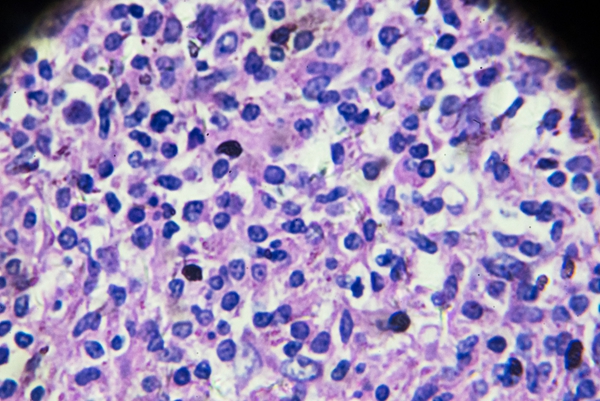

硬下疳:梅毒初期典型症状是硬下疳,通常出现在生殖器部位,如男性的阴茎、女性的大小阴唇等。表现为单个无痛性溃疡,边界清晰,基底呈肉红色,触之有软骨样硬度。

无痛溃疡:这种溃疡一般没有疼痛感,容易被患者忽视。即使不进行治疗,硬下疳也可能在几周内自行愈合,但这并不意味着梅毒已经痊愈,而是疾病进入了潜伏期。